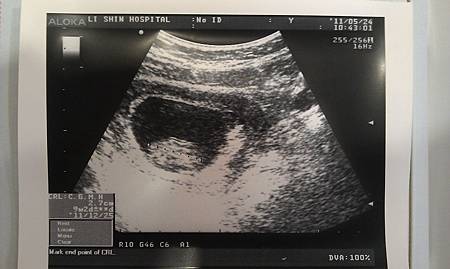

又兩周左右....

長大嚕! 有2.7cm

這樣是大約10W

終於領到媽媽手冊,感覺上有達到一個里程碑....